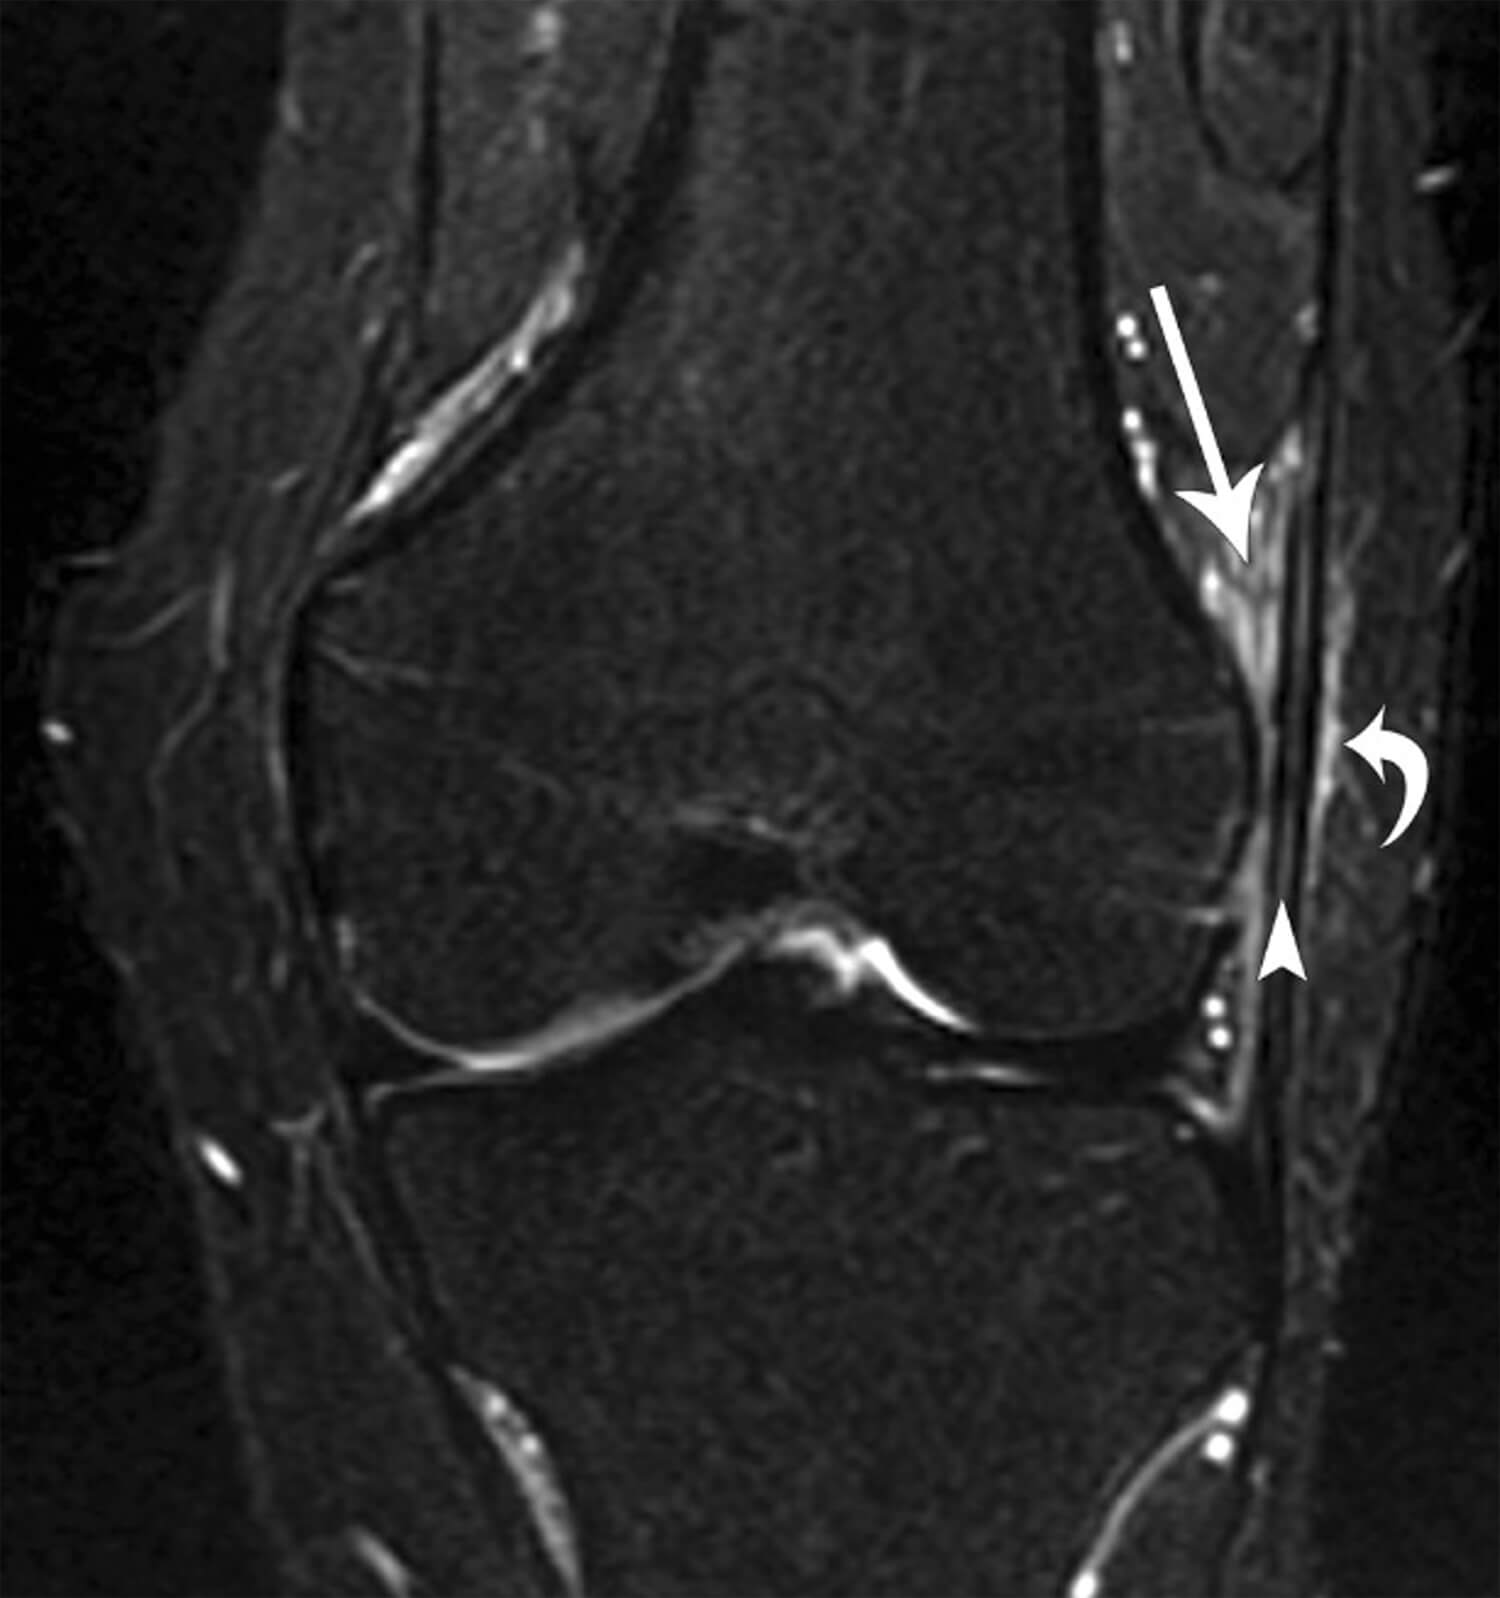

MRI scan

Ook een MRI kan de peesplaat, die verdacht wordt van klachten, in beeld brengen en beoordelen of er ergens in het bovenbeen of de knie een andere reden te vinden is voor de klachten. Belangrijk is dat niet altijd afwijkingen worden gevonden op een MRI. Deze scan kan ook puur worden gebruikt om andere redenen van de klachten uit te sluiten. Een klassiek plaatje van een MRI bij een lopersknie is dat de peesplaat verdikt is en er vocht of een slijmbeurs hieronder te zien is. Een voorbeeld hiervan zie je op het plaatje hieronder.

Een T2 opname van een MRI van de knie, waarbij de witte pijlpunt de verdikte peesplaat aan de zijkant van het bovenbeen rond de knie weergeeft en de rechte pijl en kromme pijl wijzen op vocht rond de peesplaat (Flato et al. Skelet Radiol 2017).